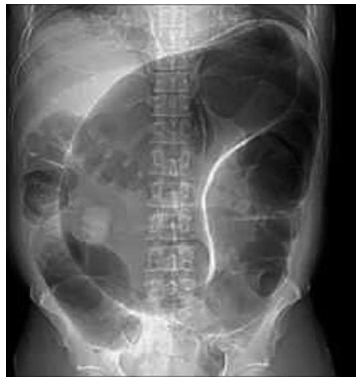

Considere-se a imagem a seguir.

Essa imagem de “U” invertido no raio-x simples de abdome é compatível com o diagnóstico de